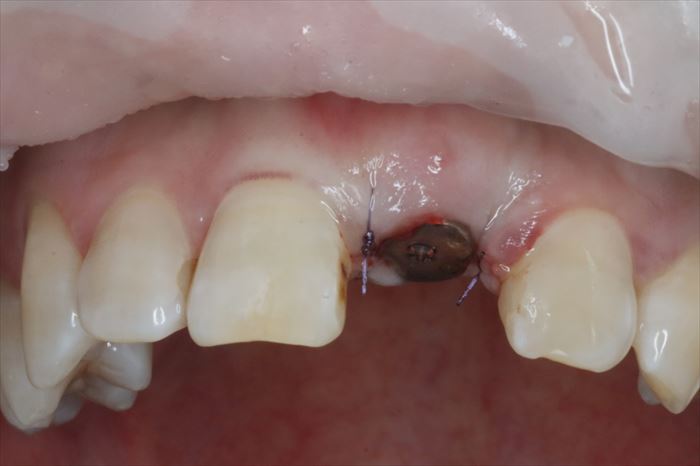

ヒーリングキャップの締結とハイドロキシアパタイトの填入を終えました。

吸収性の縫合糸で縫合を終えました。

歯肉はヒーリングキャップの形に治癒していきます。

仮歯と歯肉の隙間をレジンで埋めて、改めて両サイドと固定します。

光照射してレジンを硬化させている場面です。